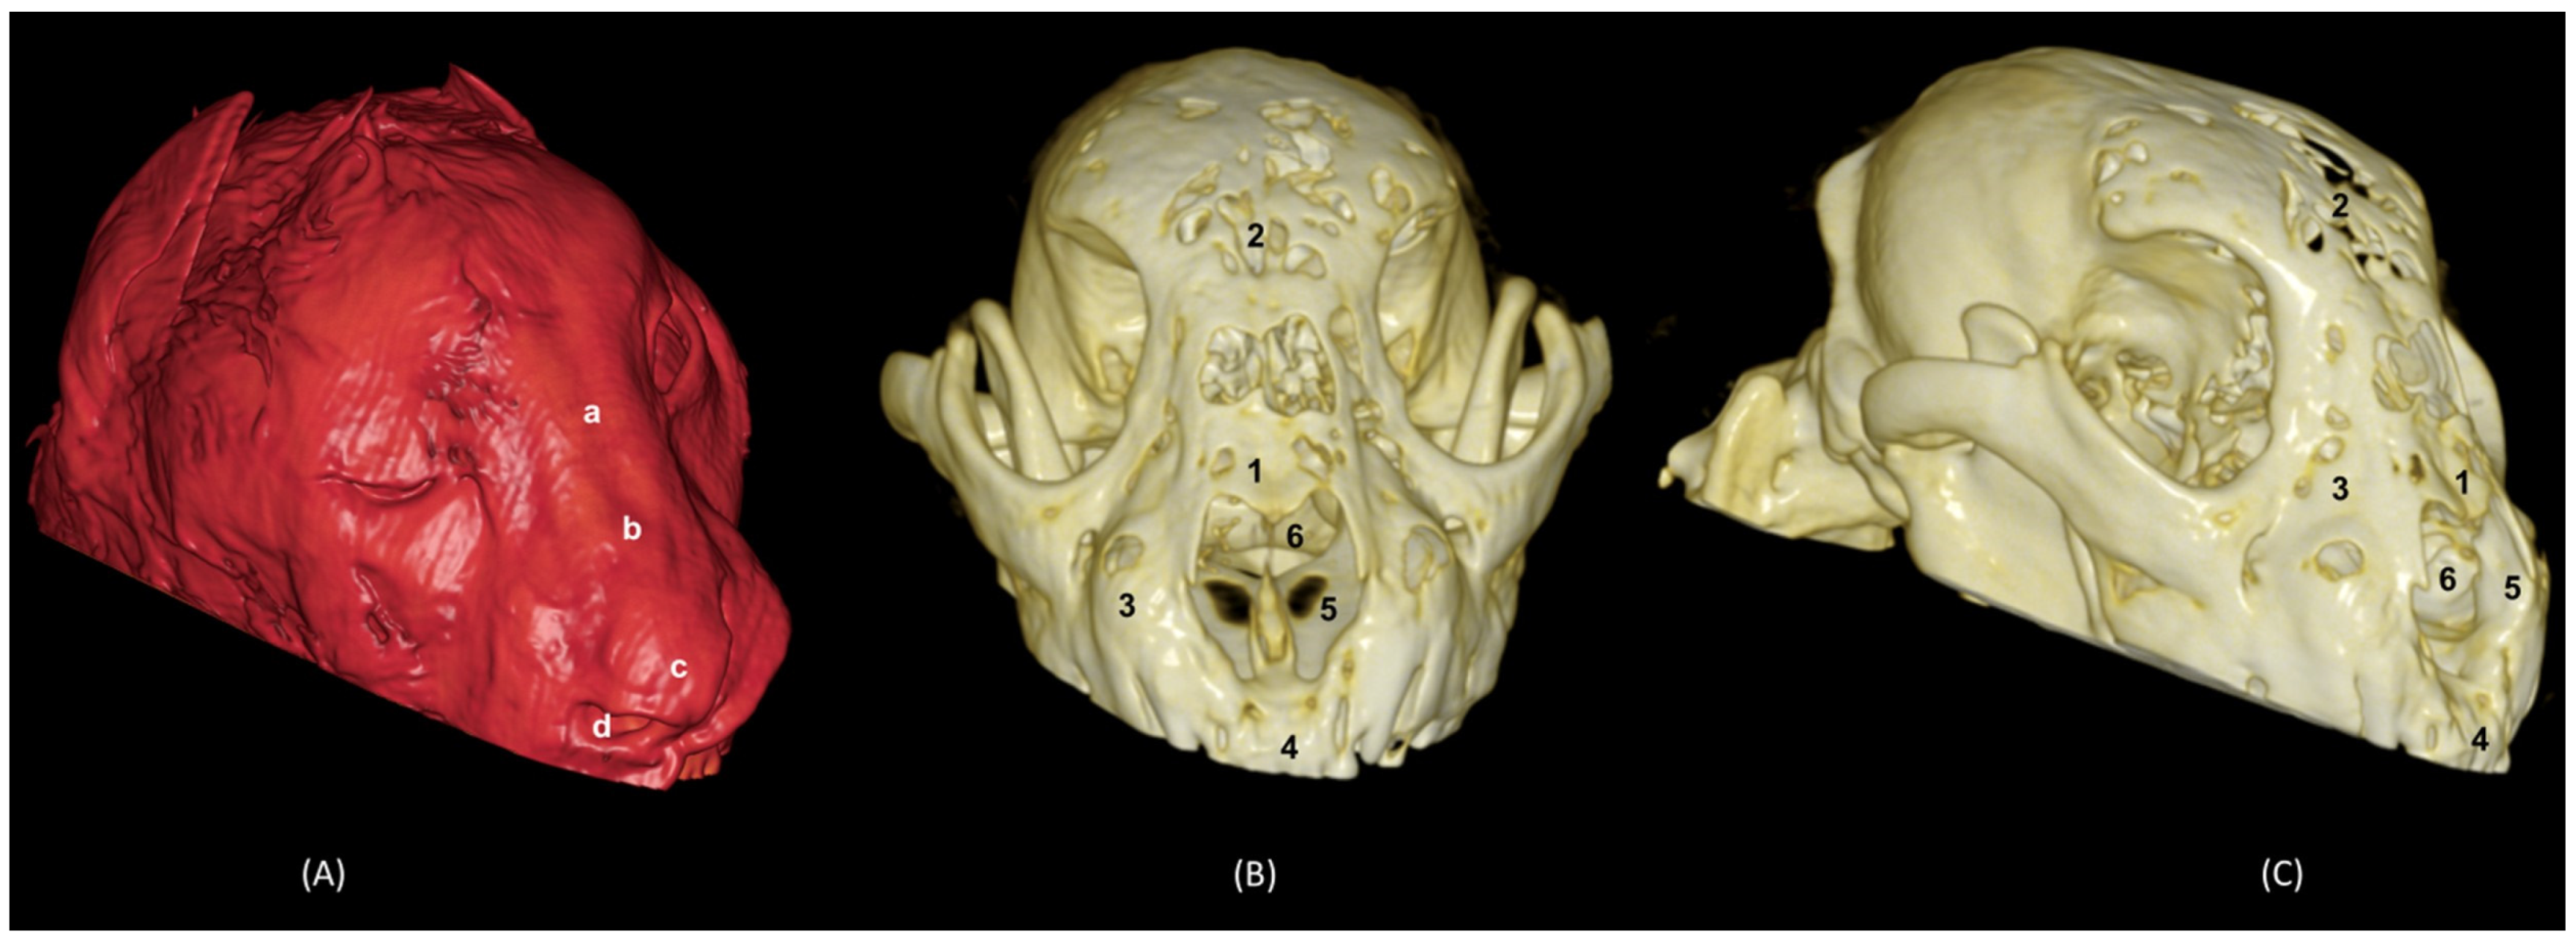

In the lion CT VR images (Figure 32), we could also observe the external nose and these bones. However, the morphology of these skulls differed from the rest. The short rostral extension of the nasal bone was observed, as well as the convex morphology that the frontal bone acquires. The bone structure was much more compact than in other felines.

Figure 32. OsiriX 3D reconstructed CT images of the lion’s head showing the external nares and nasal plane. (A): VR surface reconstruction. Rostral view. (B): VR deep reconstruction. Rostral view. (C) VR deep reconstruction. Right rostrolateral view. a. Root of the nose; b. Dorsum of the nose; c. Tip of the nose; d. Nasal orifice; 1. Nasal bone; 2. Frontal bone; 3. Maxilla; 4. Incisive bone; 5. Nasal cavity; 6. Turbinates.

In the reconstruction of the cheetah’s head (Figure 33), the limit between the frontal and nasal bones was not so pronounced. The frontal bone in the cheetah was completely concave, unlike the lion.

Figure 33. OsiriX 3D reconstructed CT images of the cheetah’s head showing the external nares and nasal plane. (A): VR surface reconstruction. Rostral view. (B): VR deep reconstruction. Rostral view. (C) VR deep reconstruction. Right rostrolateral view. a. Root of the nose; b. Dorsum of the nose; c. Tip of the nose; d. Nasal orifice; 1. Nasal bone; 2. Frontal bone; 3. Maxilla; 4. Incisive bone; 5. Nasal cavity; 6. Turbinates.

Finally, the VR reconstruction of the domestic cat skull (Figure 34) showed that the bone limits were not as noticeable as in the leopard or cheetah. The frontal bone represents a large extension since its zygomatic process developed very laterally, unlike in big felids.

Figure 34. OsiriX 3D reconstructed CT images of the cat’s head showing the external nares and nasal plane. (A): VR surface reconstruction. Rostral view. (B): VR deep reconstruction. Rostral view. (C) VR deep reconstruction. Right rostrolateral view. a. Root of the nose; b. Dorsum of the nose; c. Tip of the nose; d. Nasal orifice; 1. Nasal bone; 2. Frontal bone; 3. Maxilla; 4. Incisive bone; 5. Nasal cavity; 6. Turbinates.